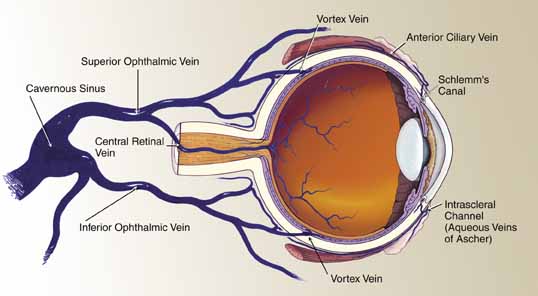

RAISED EPISCLERAL VENOUS PRESSURE

A review of the aqueous blood microcirculation of the eye (Fig. 10) explains how raised venous pressure can affect both retinal vessels and intraocular pressure. From Schlemm's canal, aqueous traverses the intrascleral emissary channels (aqueous veins of Ascher) to the episcleral plexus and then the long ciliary venous vessels. The long ciliary veins, as well as the vortex veins, empty into the ophthalmic vein before entering the cavernous sinus. Increases in episcleral venous backpressure theoretically contribute to a 1:1 mm Hg rise of measured intraocular pressure. The clinical result of an acute rise in external venous pressure may include choroidal effusion, elevated intraocular pressure with blood in Schlemm's canal (Fig. 11), and retinal vein obstruction with intraretinal hemorrhages in a central vein obstruction pattern with or without prominent swelling of the optic nerve. Chronic elevations of venous pressure may permanently damage trabecular meshwork, impairing outflow facility, and result in a chronic open-angle glaucoma.

A true shunt between the carotid and cavernous sinusoidal venous system (high-flow type) occurs in 25% of cases and usually results from trauma.56 The more common situation (75% of cases) is a vascular shunt between a dural branch of the external or internal carotid (usually meningohypophyseal branch) and the cavernous sinus (low-flow type).56 There is some evidence that vestigial dural shunts may be congenital and expand when an obstruction occurs in the transverse and sagittal venous drainage systems of the brain.56 The net effect is a direct transmittal of arterial pressure to the retinal and choroidal venous system, which may produce several syndromes. Recent work involving more precise radiologic studies suggests that the specific clinical presentation is determined by the exact location of the vascular anomaly.57 Ocular hypoxia produced by reduced flow may lead to iris neovascularization and glaucoma.58 The more common cause of elevated intraocular pressure is chronic venous pressure elevation that results in permanent damage to the trabecular meshwork. Rarely, vortex venous backpressure may produce choroidal edema, effusion, rotation of the ciliary body, and a congestive glaucoma (Fig. 12).59,60 High- and low-flow arteriovenous shunts pose no threat to human life but have been the object of prodigious surgical efforts. The indications for the surgery should remain intractable eye pain or threatened loss of the eye or other neurological deficits. Shunt flow may be reduced by arterial closure, direct shunt closure, or venous ligation. All these methods, except direct shunt closure, may exacerbate hypoxia and induce iris neovascularization.61